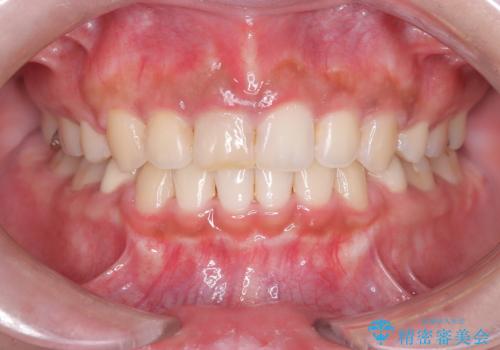

前歯の突出感を改善|上下4本の抜歯と審美ワイヤー矯正でバランスの取れた口元へ

抜歯によって前歯を下げるためのスペースを確保。その後、審美ワイヤー矯正を用いて、歯列全体のバランスを整えながら前歯を後方へ移動させました。治療後は、横顔のラインが整い、自然な口元になったことで、見た目も噛み合わせも改善しました。患者様からは「口元がすっきりして、自信を持って笑えるようになった」と喜びの声をいただきました。